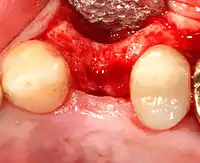

يجب أن تكون الغرسة محاطة بكمية مناسبة من العظام من أجل الألتحام والبقاء على المدى الطويل، بالإضافة إلي وجود غلاف سميك من الأنسجة الرخوة الصحية (اللثة) حوله. من الشائع أن تكون العظام أو الأنسجة الرخوة ناقصة جدًا بحيث يحتاج الجراح إلى إعادة بنائها إما قبل أو أثناء وضع الغرسة.[29]

إعادة بناء العظام

تطعيم (ترقيع) العظام ضروري عندما يكون هناك نقص في العظام كما أنه يساعد على استقرار الغرسة في مكانها علي المدي الطويل وتقليل فقدان مستوى العظام في الهوامش. لتحقيق عرض وارتفاع كافيين للعظم، تم تطوير العديد من تقنيات تطعيم العظام. فترقيع العظام يتم بملء العيب إما بالعظام الطبيعية المحصودة أو بديل عظمي صناعي، مغطى بغشاء شبه نفاذ ويسمح له بالالتئام. و خلال مرحلة الشفاء، يستبدل العظم الطبيعي العظم المستخدم في الترقيع ليشكل قاعدة جديدة للغرسة.[30] في حين أن هناك دائمًا أنواع جديدة من الغرسات، مثل الغرسات القصيرة (ذات القطر المنخفض)، وتقنيات للسماح بحلول وسط لوضع غرسات، فإن هدف العلاج العام هو أن يكون الحد الأدنى لارتفاع العظم 10 مم، وعرض 6 مم.[31]